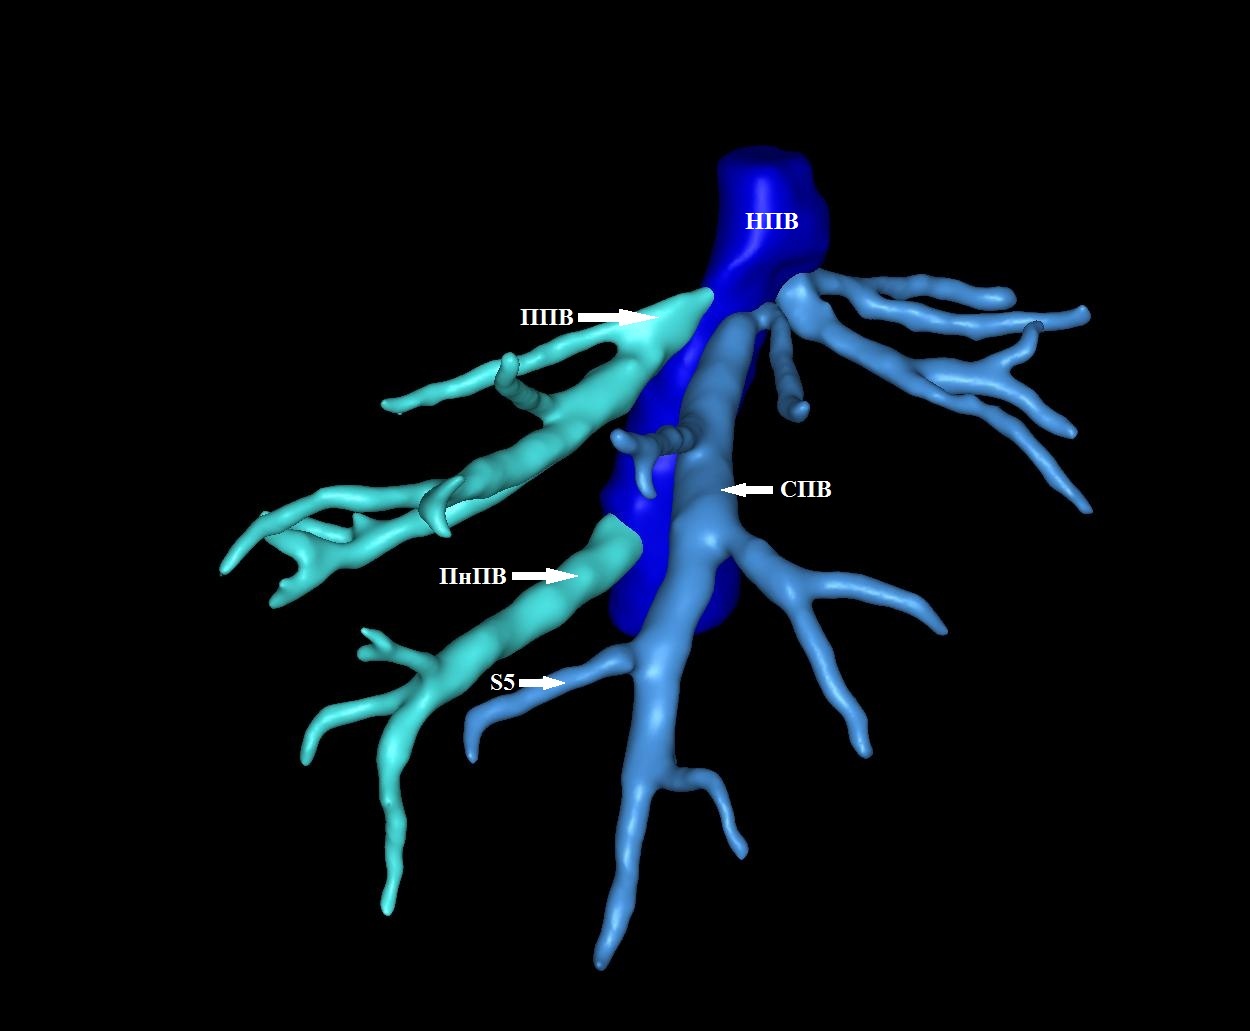

Результаты. Выявлено 14 подтипов анатомии эфферентных сосудов. Их классифицировали в 3 типа в зависимости от вклада срединной вены в отток крови от правой доли печени: кавальный (67,3%), кава-срединный (полусепаратный, 29%) и сепаратный (3,6%).

5. Тип B (схема). | |

| Тема | ||

| Тип | Исследовательские инструменты | |

Посмотреть

(1MB)

|

Метаданные ▾ | |